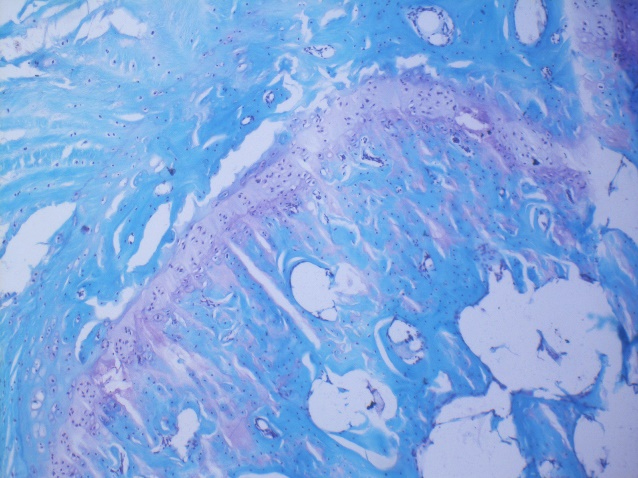

碧云天生产的番红O-固绿软骨染色试剂盒是一种能高效、灵敏、快速将软骨组织与骨组织进行染色区分的试剂盒。本试剂盒采用的是番红O-固绿染色法,通常适用于组织的石蜡切片。

番红O(Safranine O)是一种阳离子染料,可与软骨蛋白多糖中阴离子基团(硫酸软骨素或硫酸角质素)结合呈现红色、紫红色或紫色以显示软骨。当软骨受到损伤时,软骨中的糖蛋白会释放出来,使基质成分分布不均匀,从而导致番红O淡染或不着色;

固绿(Fast green)是一种酸性染料,与嗜酸性的骨组织结合而呈现绿色或蓝色,从而将软骨组织与骨组织区分开。